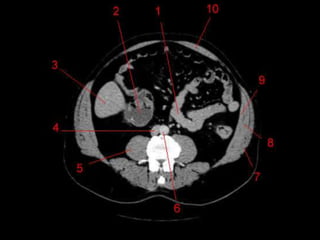

Subdivisão Funcional

• Alem de anatômico, os lobos direito e

esquerdos são divididos funcionalmente.

– Cada um recebe sua tronco primário da artéria

hepática, tem sua própria veia portal e drena para

o seu próprio ducto hepático.

• Caudado também funciona separadamente.

– “Terceiro fígado”

• Depois pode ser divido em 4 partes e 8

segmentos ressecáveis cirurgicamente.

Subdivisão Funcional • Alemde anatômico, os lobos direito e esquerdos são divididos funcionalmente. – Cada um recebe sua tronco primário da artéria hepática, tem sua própria veia portal e drena para o seu próprio ducto hepático. • Caudado também funciona separadamente. – “Terceiro fígado” • Depois pode ser divido em 4 partes e 8 segmentos ressecáveis cirurgicamente.

Subdivisão Funcional • Fundamentalimportância para Ressecção. • Maioria das lesões são do fígado direito.